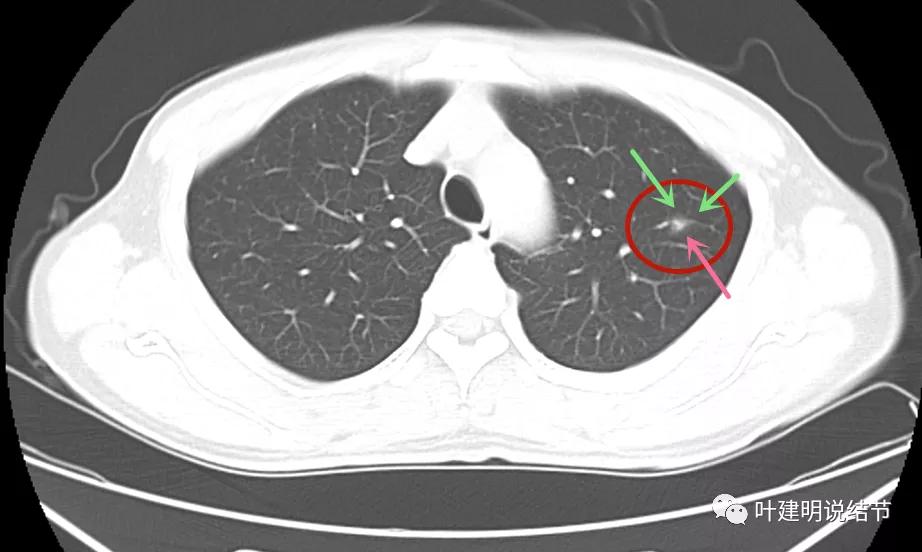

但可惜当时不是薄层扫描的。后来口服莫西沙星6天,并于2021年11月复查的是薄层的:

病灶1几乎没什么变化,实性部分范围感觉略大,显模糊。我考虑是因为薄层的关系,不是病灶有明显变化,轮廓仍是不清的

病灶2仍是极淡的,但也没有消失,有微血管贴边走行,间隙不清,此灶倒是要考虑不典型增生之类的范畴的病灶,虽然小又淡。

病灶3较前感觉明显了点,但我仍考虑也是扫描条件不同的关系,不能认为是进展。